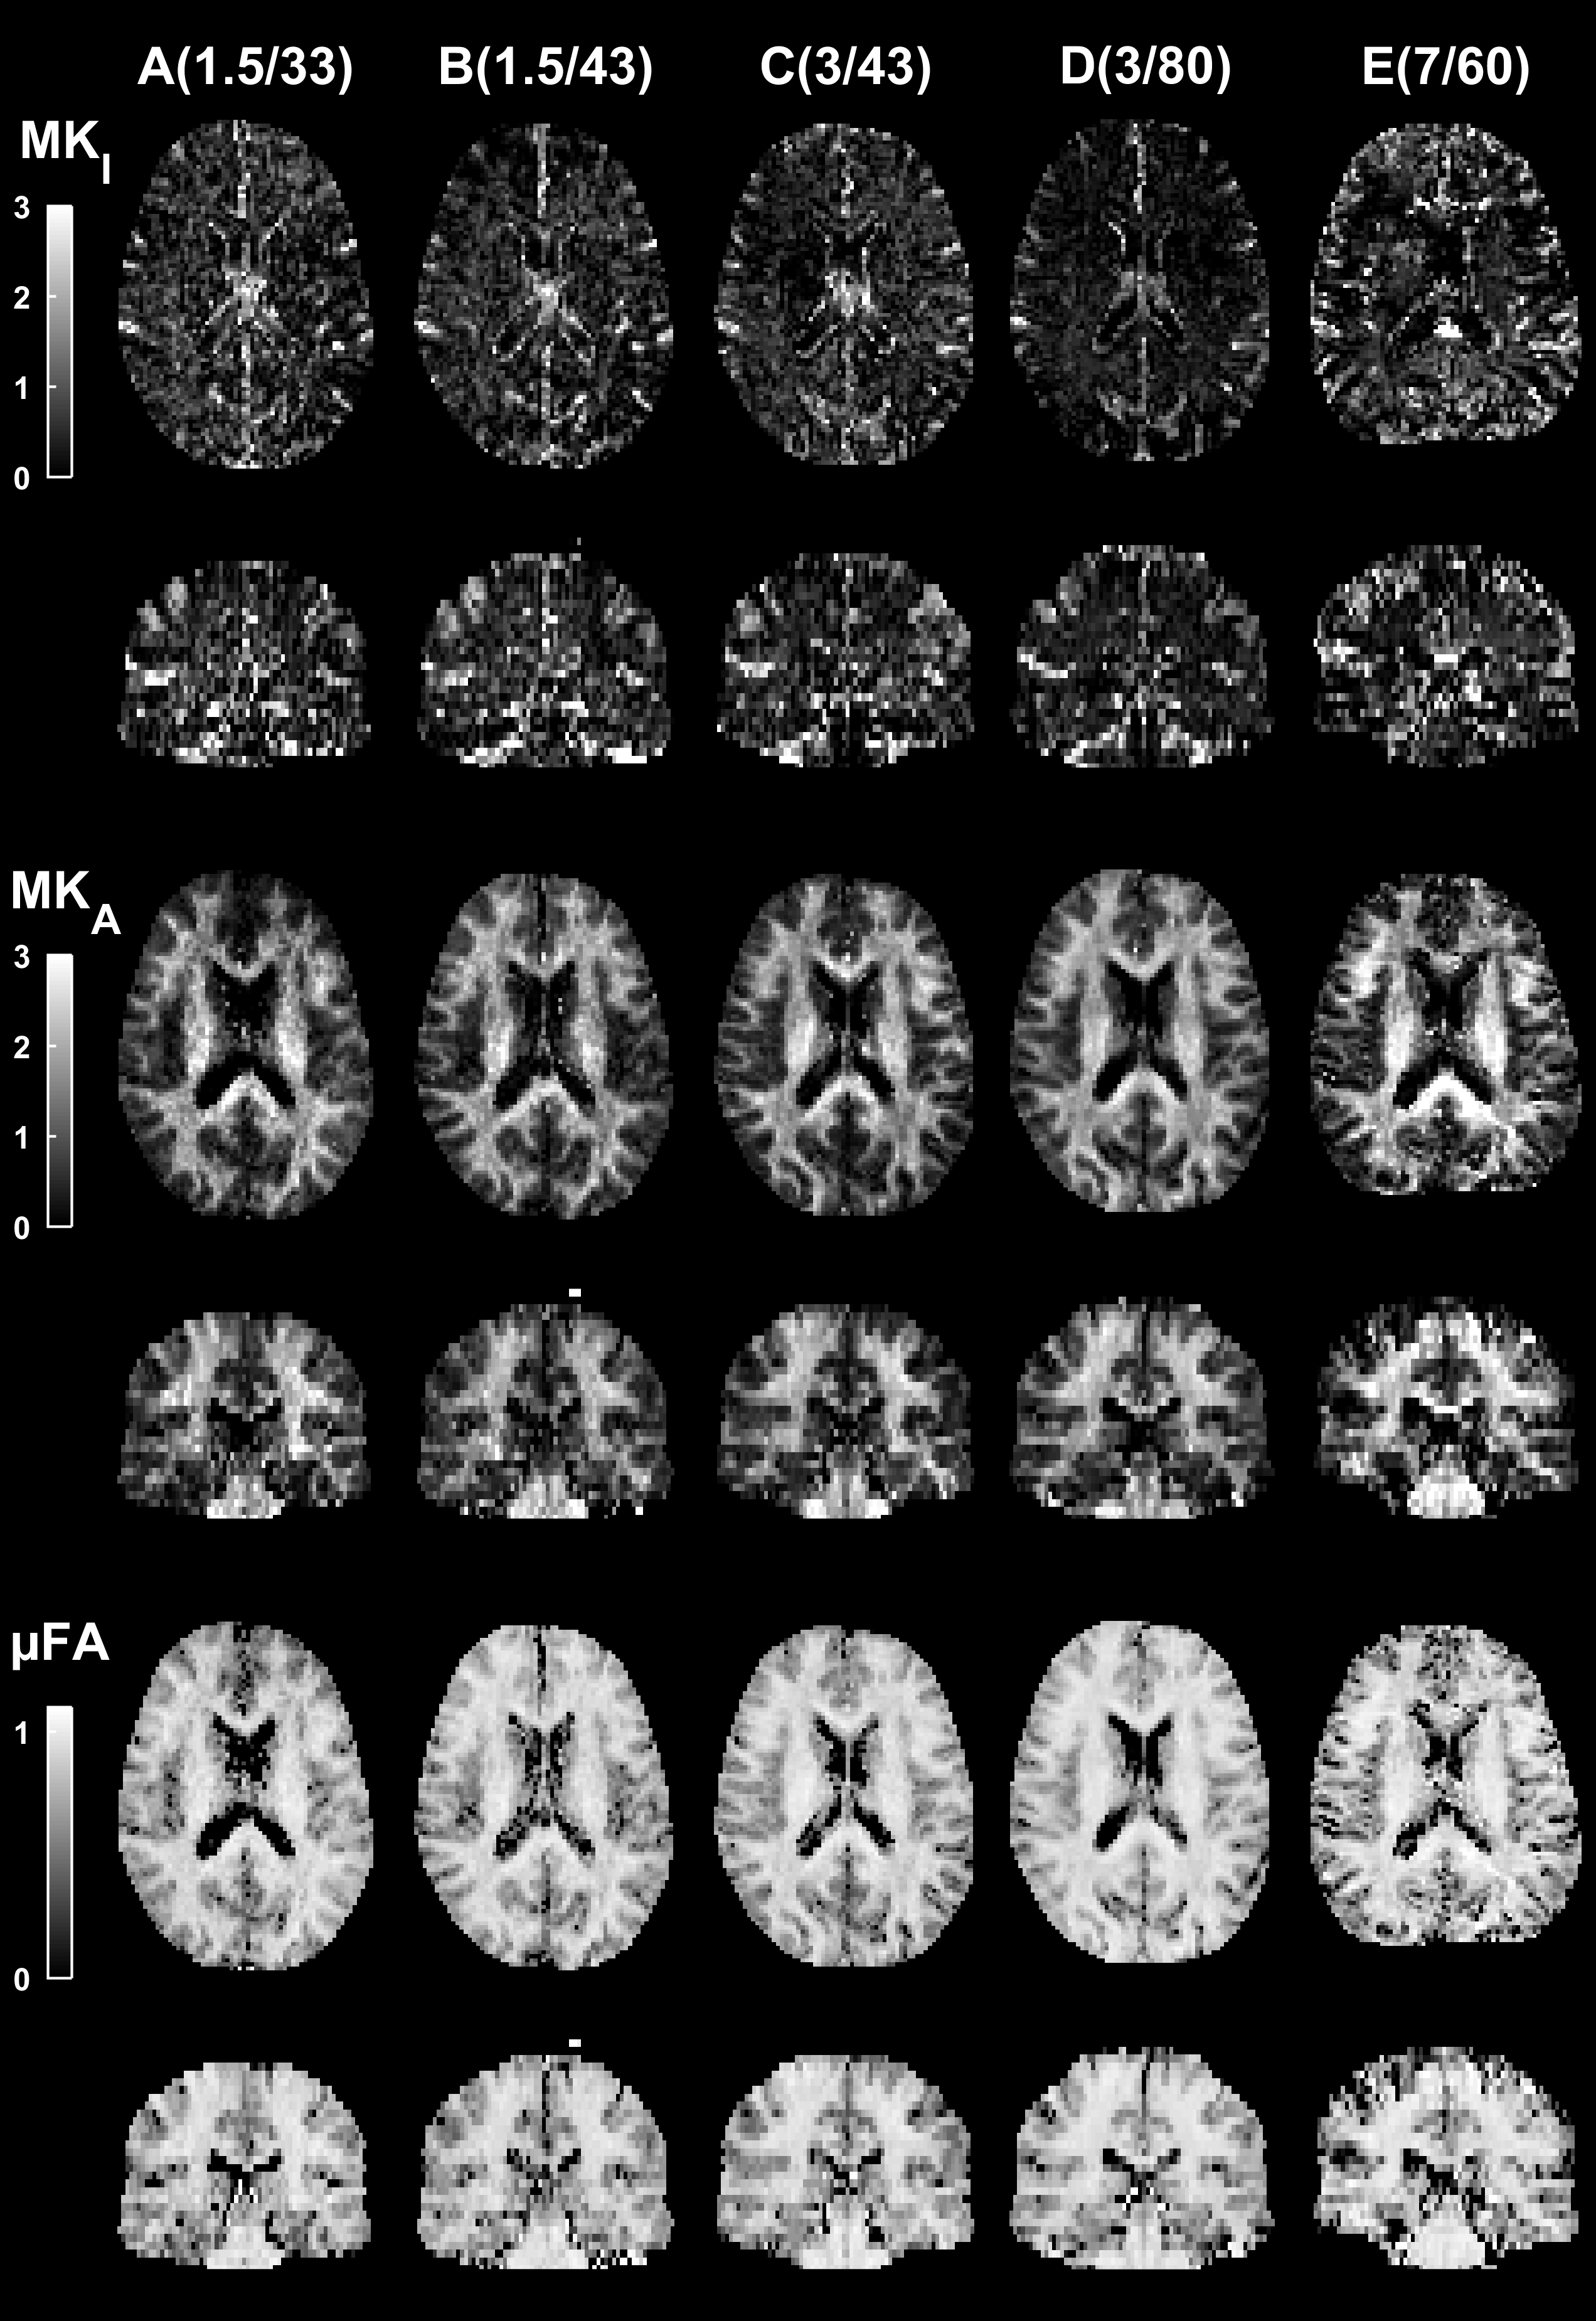

Illustrations